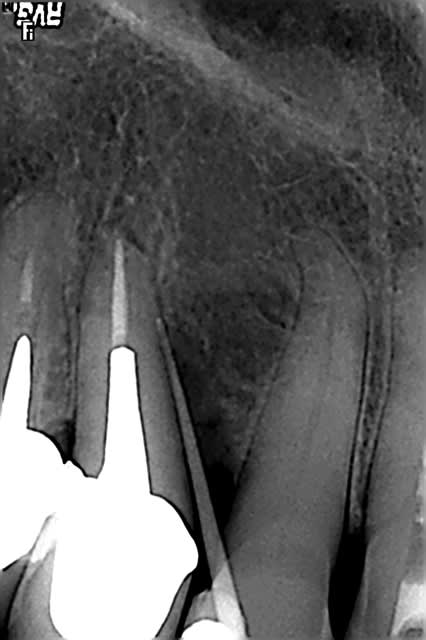

Voila, tout est dans le titre, une patient avec une dent re-implanté suite accident de voiture en 1990. Resorption externe et semble ( comme la 12 ) completement ankylosée.

Vous gerez cela comment ?

Je pense en fait bouffer la dent a la fraise pour economiser l'os alvéolaire, car si l'on part sur de l'alvéoltecmie, on se dirige plutot vers une greffe ensuite, non ?

Si je fraise la dent, puis je passe mes forets et pose l'implant, c'est grave, docteur si j'ai oublié des bouts de dent ? ( la limite dent-os est pas toujours évidente, même si l'os, ça saigne et pas la dent ).